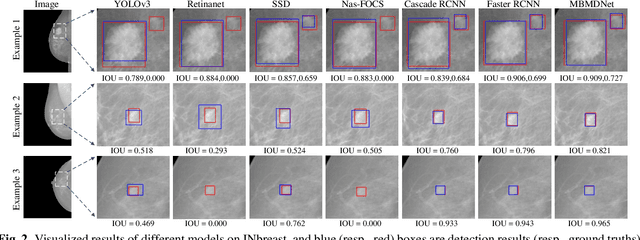

Multi-Head Feature Pyramid Networks for Breast Mass Detection

Feb 22, 2023

Analysis of X-ray images is one of the main tools to diagnose breast cancer. The ability to quickly and accurately detect the location of masses from the huge amount of image data is the key to reducing the morbidity and mortality of breast cancer. Currently, the main factor limiting the accuracy of breast mass detection is the unequal focus on the mass boxes, leading the network to focus too much on larger masses at the expense of smaller ones. In the paper, we propose the multi-head feature pyramid module (MHFPN) to solve the problem of unbalanced focus of target boxes during feature map fusion and design a multi-head breast mass detection network (MBMDnet). Experimental studies show that, comparing to the SOTA detection baselines, our method improves by 6.58% (in AP@50) and 5.4% (in TPR@50) on the commonly used INbreast dataset, while about 6-8% improvements (in AP@20) are also observed on the public MIAS and BCS-DBT datasets.